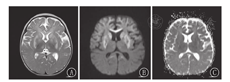

入院查体:神志清,有注视,竖颈不稳,双侧巴氏征阳性,余查体未见明显异常。辅助检查:2次血乳酸均升高,分别为5.81 mmol/L、5.25 mmol/L(正常范围0.5~1.7 mmol/L)。血串联质谱、尿有机酸均未见明显异常。视频脑电图异常:(1)清醒期两额区10~11 Hz α活动短程阵发;(2)睡眠期两额区不规则尖波。头颅磁共振成像(MRI):双侧基底核区、胼胝体、额叶、侧脑室前角周围及大脑脚对称性病变(图1),考虑代谢性疾病可能。根据患儿临床表现及视频脑电图结果,初步诊断继发性癫痫。因病因未明,行癫痫基因及代谢性疾病基因检查。